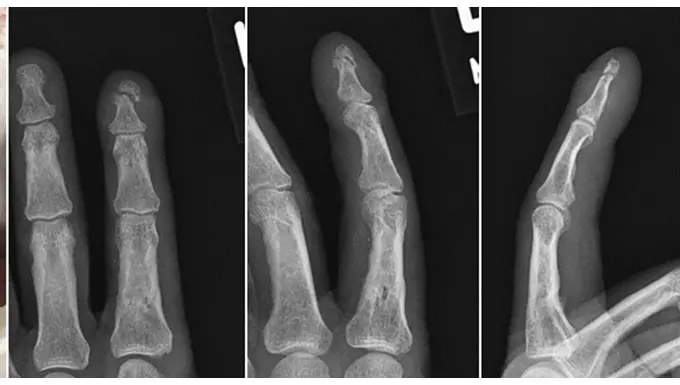

What Is a Distal Phalanx Fracture?

The distal phalanx is the bone at the tip of your finger. It supports the nail and plays a key role in fine motor skills like gripping and pinching.

Fractures here are commonly:

- Tuft fractures (tip of the bone, often crushed)

- Shaft fractures (middle part)

- Base fractures (near the joint, sometimes involving tendons)